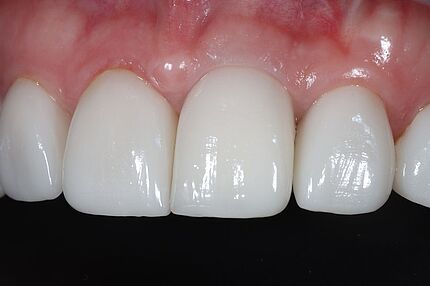

Im Journal Zahnmedizin up2date demonstrieren unsere Ästhetik-Spezialisten in einem weiteren Beitrag zum Thema professionelle Zahnaufhellung wie ein entsprechend angeleitetes At-Home-Bleaching funktioniert. Die entscheidende Vorbereitungsphase mit der Herstellung der Schienen und der adäquaten Instruktion des Patienten werden in dieser Publikation anhand eines Bildessays illustriert.

In der Ausgabe 02/2023 der Fachzeitschrift Zahnmedizin up2date berichten unsere beiden Ästhetik-Spezialisten wie ein professionelles In-Office-Bleaching vitaler Zähne funktionieren kann. Die hierzu nötigen Arbeitsschritte einschließlich der klinischen Voraussetzungen werden Schritt für Schritt anhand eines Bildessays illustriert.